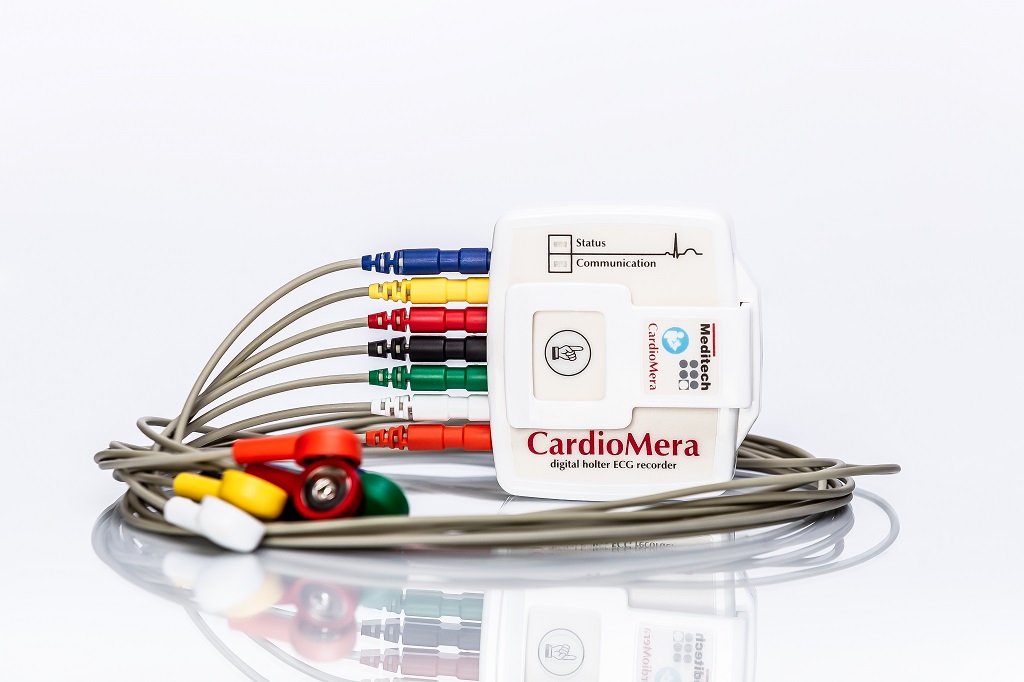

TLC9803 Dynamic ECG Systems

TLC9803 Dynamic ECG Systems

DYNAMIC ECG SYSTEM - TLC6000

DYNAMIC ECG SYSTEM - TLC6000

MEDITECH CARDIOMERA ECG Holter monitor

MEDITECH CARDIOMERA ECG Holter monitor